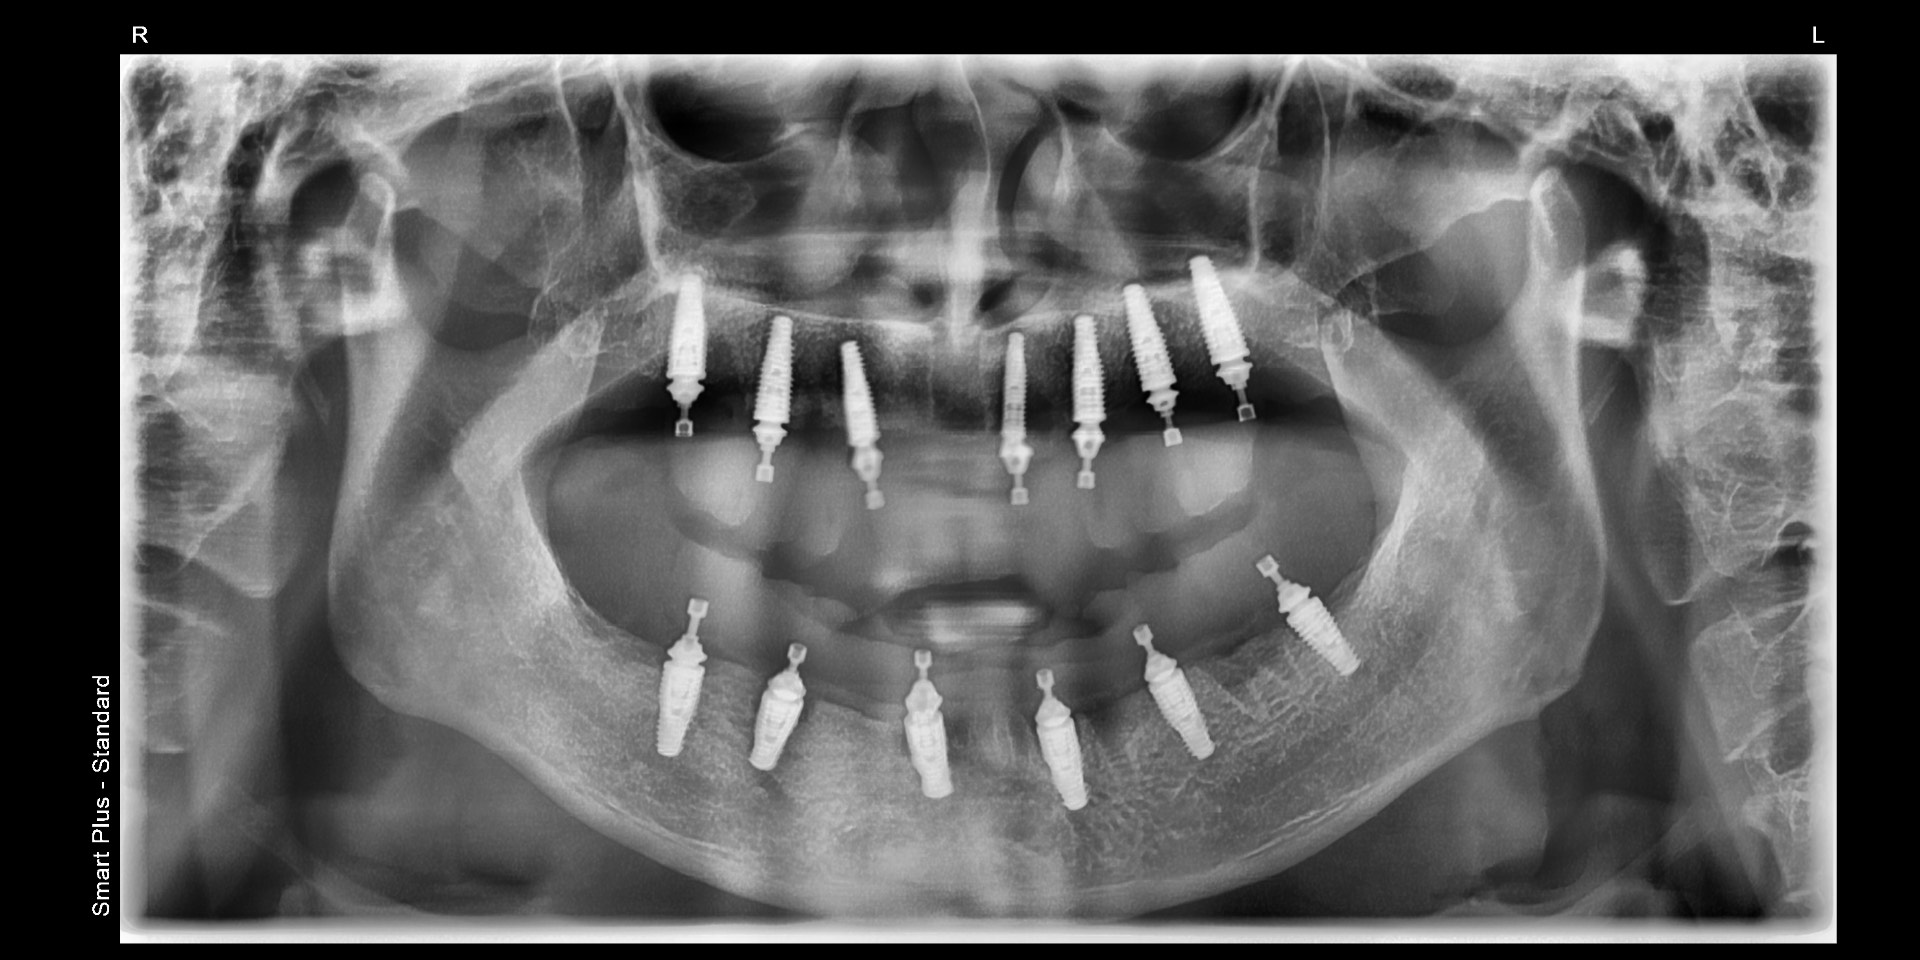

Advanced Care: LANAP Laser & Dental Implants in Harmony

At sunrise family dental, we combine LANAP laser periodontal therapy with dental implant technology to provide patients with a comprehensive oral health solution. LANAP offers a minimally invasive treatment for periodontal disease and promotes gum and bone regeneration, while dental implants provide long-lasting and stable restoration for missing teeth. Together, these advanced techniques not only help preserve natural teeth but also rebuild missing dentition, restoring a healthy and confident smile.